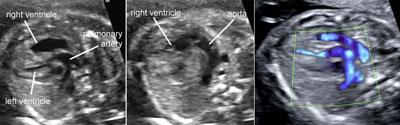

Two-dimensional gray scale imaging of fetal cardiac connections

Legend:Two-dimensional gray scale imaging of fetal cardiac connections

Color Doppler of fetal cardiac connections

Legend:Color Doppler of fetal cardiac connections